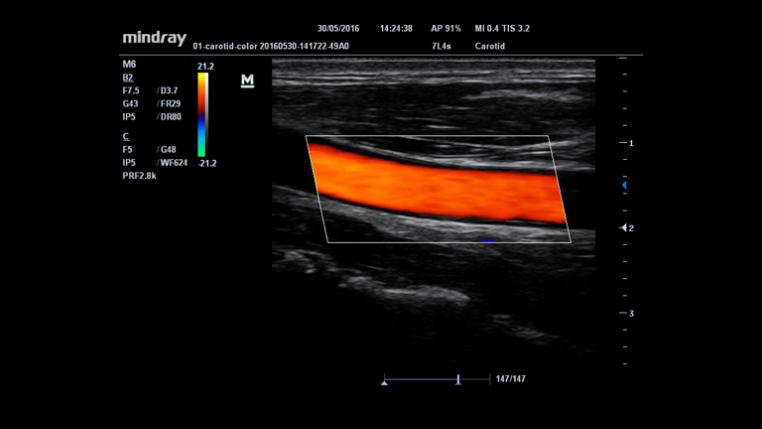

Auto measurement of anterior and posterior wall thickness providing accurate carotid status.